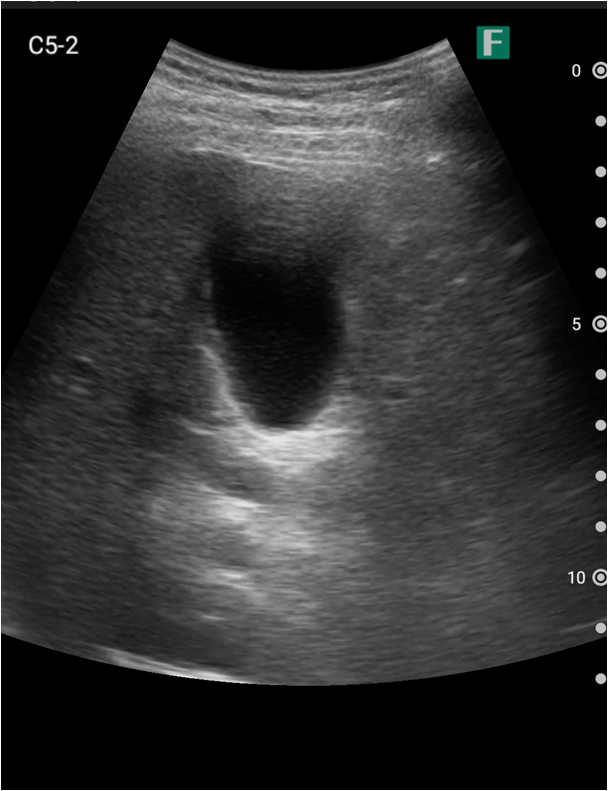

夜間、腹痛を主訴に高齢の男性が救急外来にいらっしゃいました。その方は尿道カテーテルが入っており、頻繁にカテーテルの閉塞を起こしている病歴がありました。

視診を行い下腹部に軽度の膨隆が確認できましたが体外から出ているカテーテルには明らかな閉塞を認めませんでした。そこで、iViz airで観察したところ、膀胱内に約400mlの残尿を認めカテーテル閉塞による腎後性腎不全と診断を確定させることができました。尿道カテーテルを抜去した際、外見からは見えないカテーテルの先端部分に沈殿物を認め、閉塞の原因であるとわかりました。その後尿道カテーテルの交換を行うと残尿の排出ともに腹痛は消失し、無事に帰宅されました。iViz airでの観察が尿閉の確定診断につながった症例です。